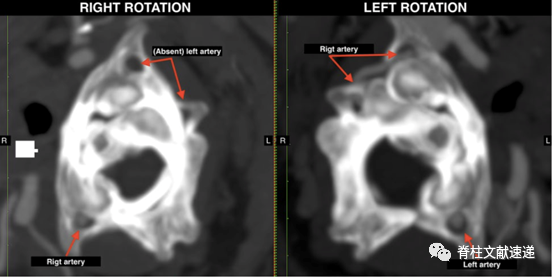

3)固定融合术:对于寰枢椎不稳或其他椎体不稳导致的BHS,诊断明确后,固定融合是有效的治疗方法。如下图所示。

图注:CTA冠状位:左图为头部中立位时,双侧椎动脉可见;右图为头部右转时,右侧椎动脉可见,左侧V3段椎动脉闭塞。

图注:CTA轴位:左图为头部右转时,右侧椎动脉可见,左侧V3段椎动脉闭塞。右图为头部左转时,双侧椎动脉可见。该患者行C1/2固定融合术,症状缓解。